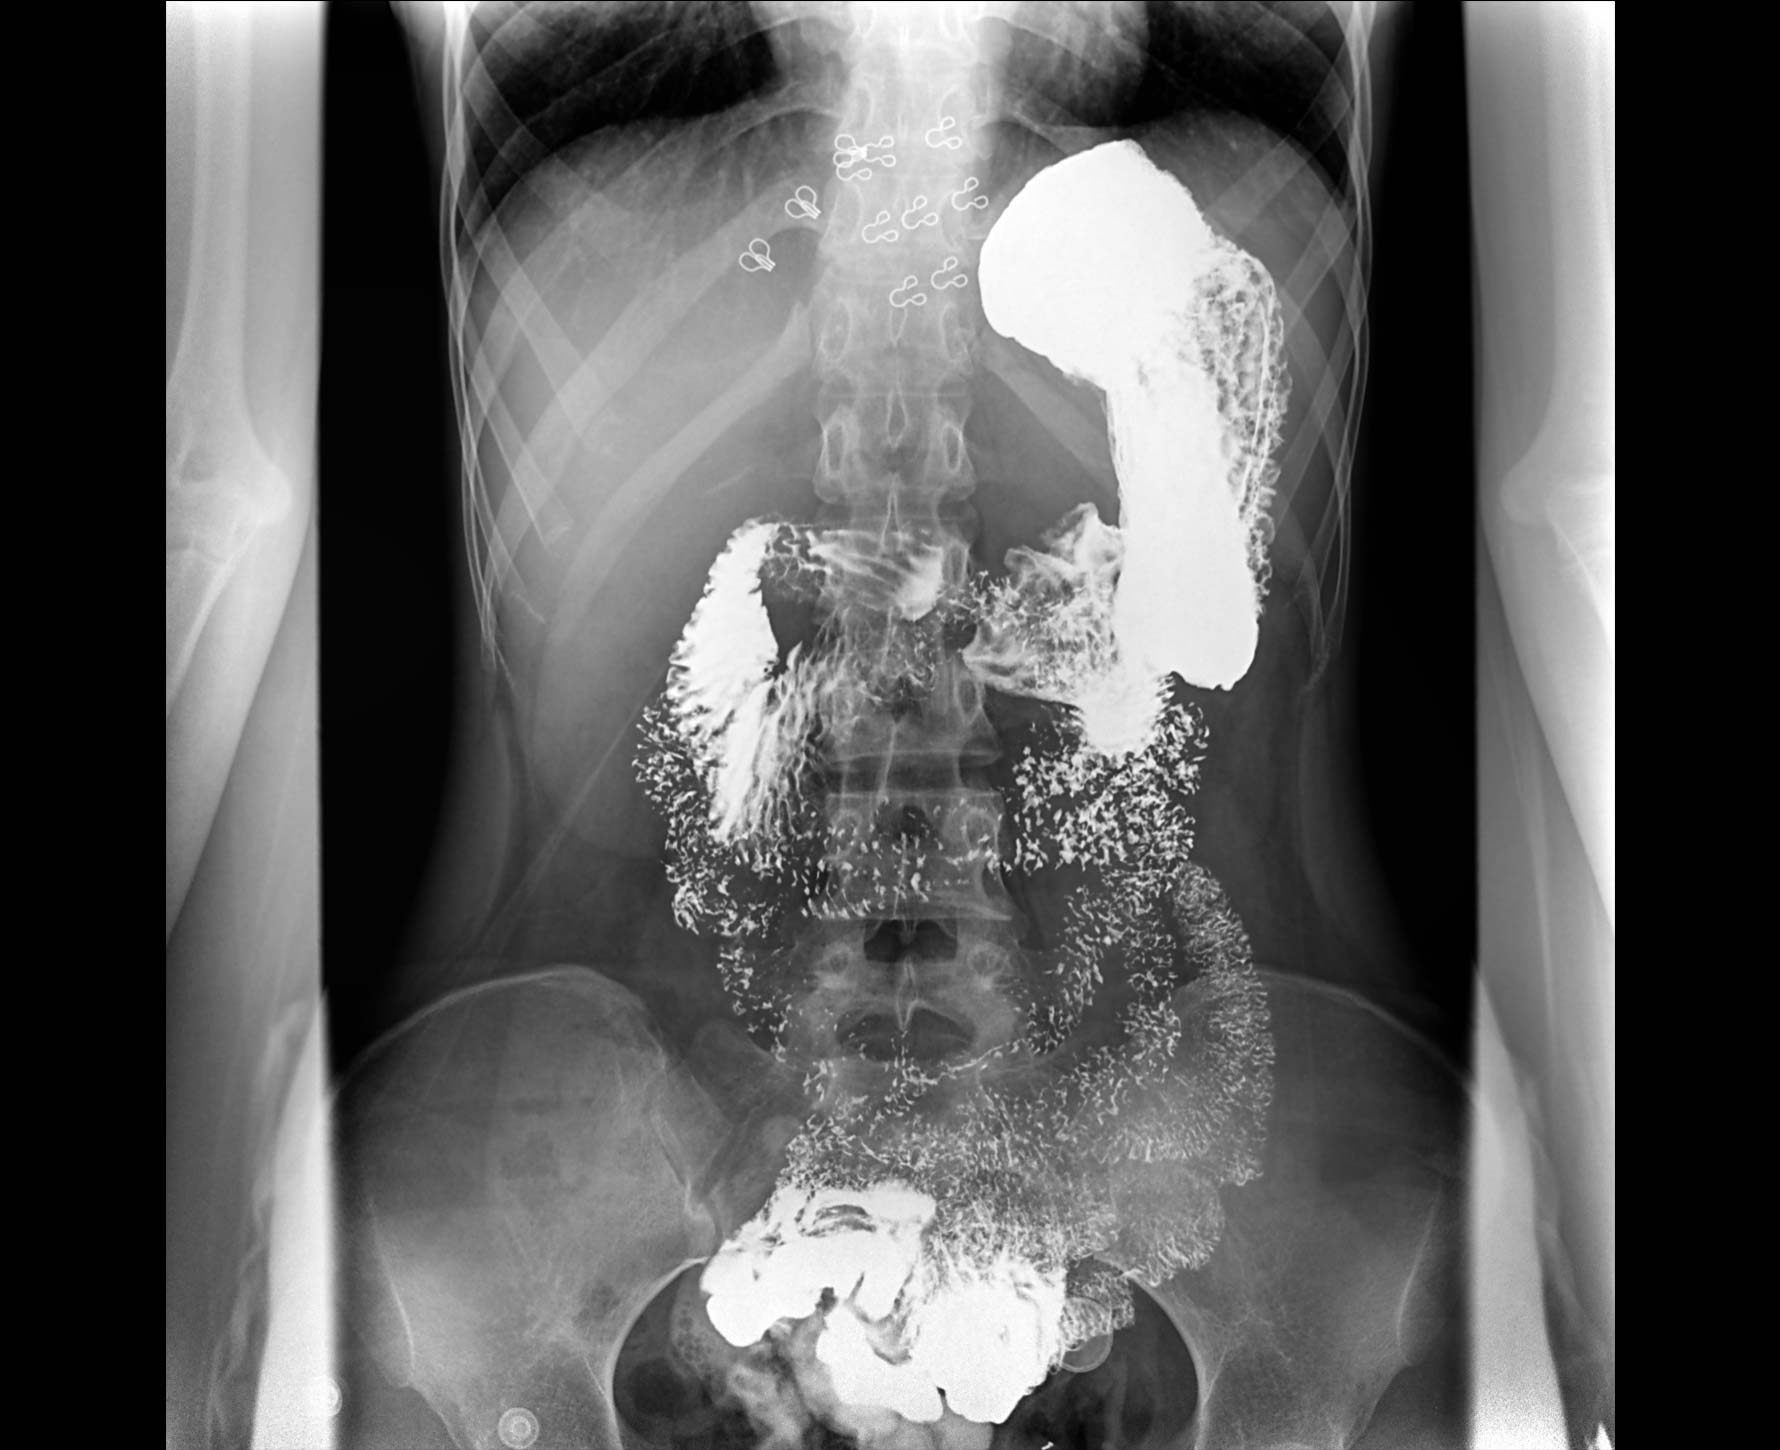

適用于各種普通

及特殊胃腸造影檢查

對胃腸造影檢查影像實時保存,多次回放以便確定病灶部位,患者確診好幫手,減少漏診。